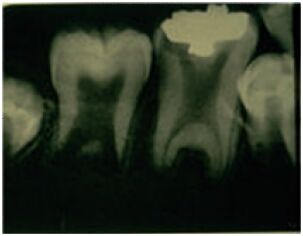

67.病人主訴牙齒容易移位及脫落,其局部根尖片顯示如圖,此病人最可能罹患何種疾病?

(A)局部牙齒發育不良(regional odontodysplasia) (B)第一型牙本質發育不良(dentin dysplasia type I) (C)第二型牙本質發育不良(dentin dysplasia type II) (D)牙本質形成不良(dentinogenesis imperfecta)